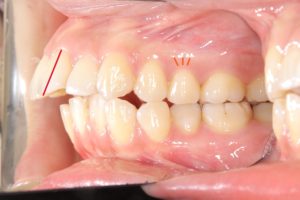

矯正治療前

赤い線が切端ライン

青い線が歯頚部ラインです。

抜歯後8カ月経過

唇側に向いていた切端ラインが

抜歯後内側(口蓋側)に向いています。

このように前歯を後退できるのは

精密検査時のCTデータで

骨の厚み、歯根の位置を立体的に把握し

前歯を下げても骨や歯肉に無理が生じないことを

事前に確認した上で治療を行うからです。